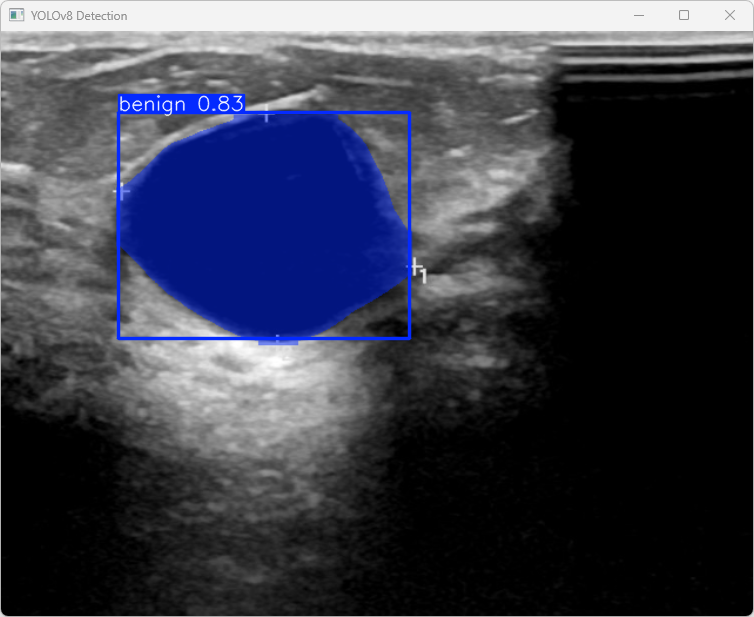

执行imgTest.py代码后,会将执行的结果直接标注在图片上,结果如下:

这段输出是基于YOLOv8模型对图片“benign (9).png”进行检测的结果,具体内容如下:

图像信息:

(1)处理的图像路径为:TestFiles/benign (9).png。

(2)图像尺寸为512×640像素。

检测结果:

(1)模型在图片中检测到:检测到 1个良性(benign)目标。

处理速度:

(1)预处理时间: 3.5 毫秒

(2)推理时间: 44.1 毫秒

(3)后处理时间: 60.0 毫秒

总结:

模型的分割推理速度较快,整体时间(约107ms)适合实时检测场景。